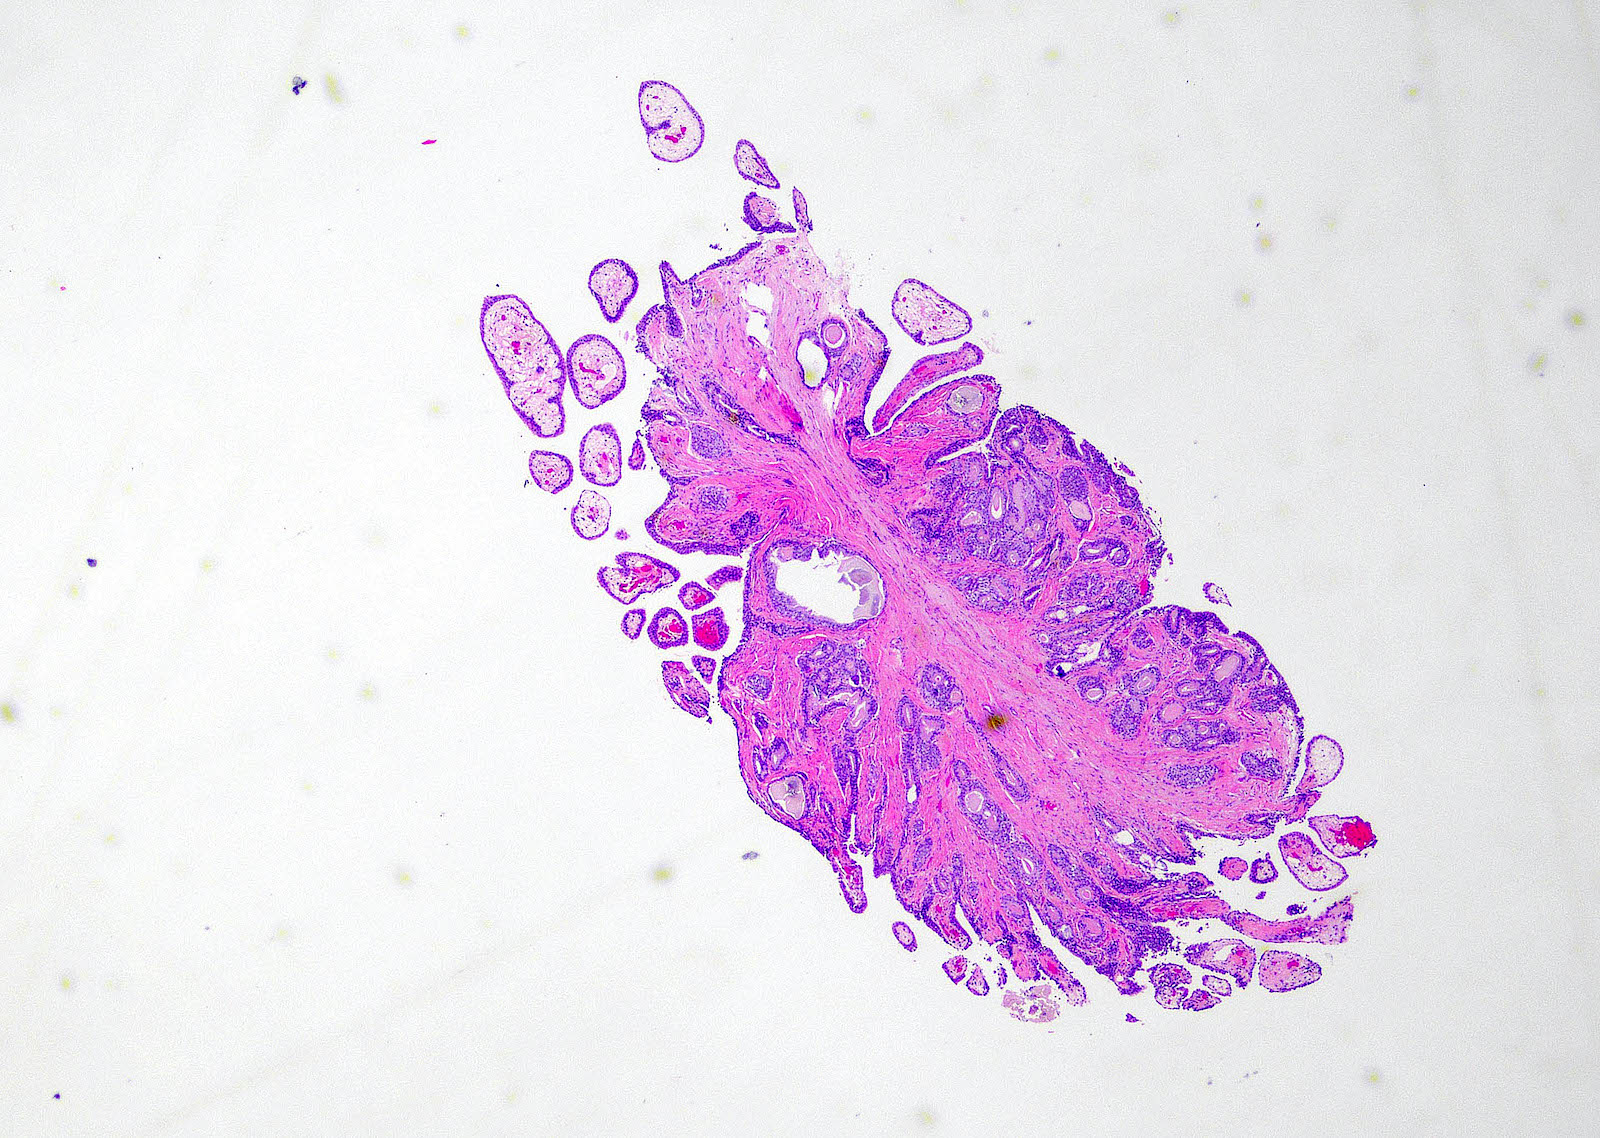

Microscopic (histologic) images

Contributed by Y. Albert Yeh, M.D., Ph.D.

Fibroepithelial polyp